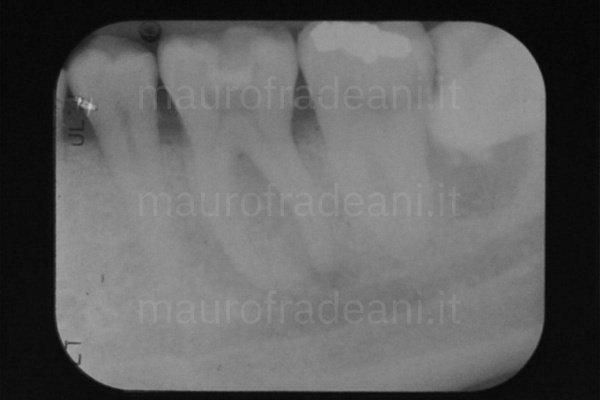

1/2: Despite already having devitalized the tooth, the patient presents tooth pain and feels gum swelling; a new root canal therapy is therefore necessary.

2/2: The post-operative X-ray shows an adequate root canal therapy, solving all symptoms previously reported by the patient.